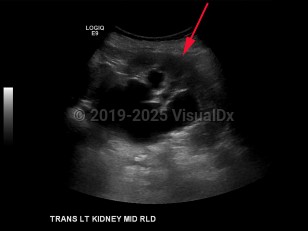

Hydronephrosis in Adult

Nephrolithiasis, prostatic hypertrophy or carcinoma, and retroperitoneal or pelvic neoplasms are the most common causes of hydronephrosis in adults. In children, hydronephrosis is most often secondary to an anatomic abnormality such as posterior urethral valves, vesicoureteral reflux, or ureteropelvic junction (UPJ) obstruction. Bilateral hydronephrosis is most often secondary to bladder tumors that obstruct the outflow of urine. In women, this can be caused by uterine, cervical, or ovarian cancer. Congenital anomalies account for a higher incidence of hydronephrosis in children compared to adults.

The Society for Fetal Urology has developed a grading system for severity of hydronephrosis. Grades range from 0-4; grade 0 is the most mild with no renal pelvis dilation, and grade 4 is the most severe and is characterized by dilation of the renal pelvis and calyces and thinning of the renal parenchyma.